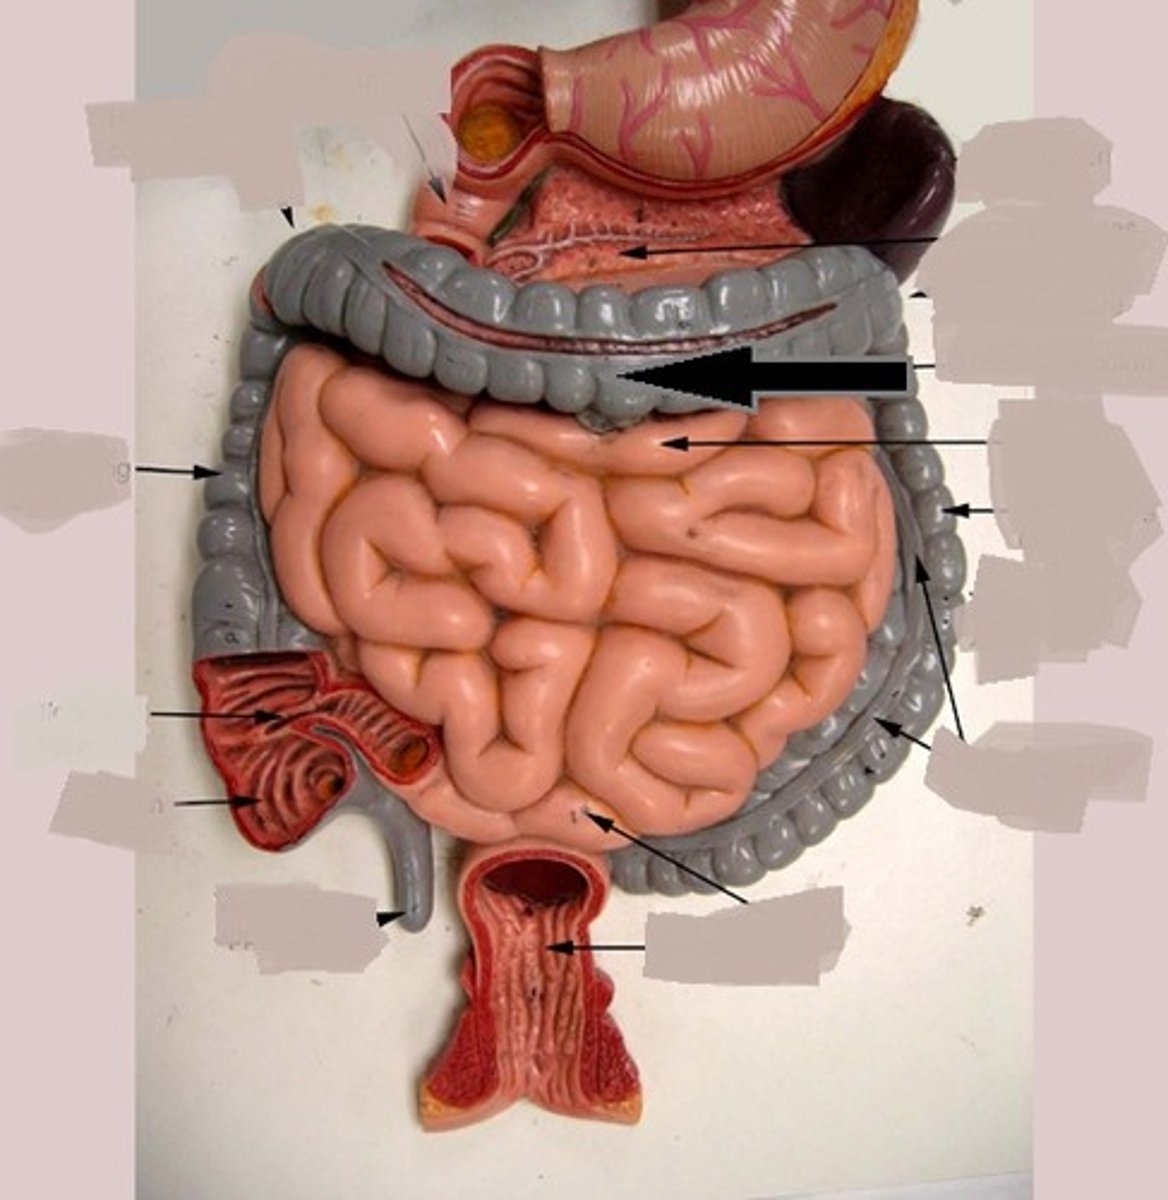

large intestine

cecum

Specific

cecum

ascending colon

Specific

transverse colon

Specific

descending colon

Specific

sigmoid colon

specific

illeocecal valve

Apendix

haustrum / haustra

taeniae coli

rectum

E